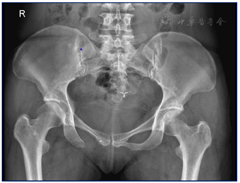

体格检查:体温36.5℃,心率90次/min,呼吸18次/min,血压130/90 mmHg(1 mmHg=0.133 kPa),心肺腹查体未见异常。专科检查:右髋部皮肤完好无破溃,无畸形及肿胀,肌肉无萎缩,骨盆无倾斜,双下肢基本等长;右侧腹股沟中点处压痛(+),叩痛(+),未触及肿块,髋关节周围轻度叩痛,下肢纵向叩击痛(±),右下肢皮温血运良好,足背动脉及胫后动脉搏动可触及;右髋关节屈曲、外展、外旋活动略受限,肌力Ⅳ级,膝关节、踝关节活动正常;右下肢直腿抬高试验及加强试验、大腿滚动试验、"4"字试验均阴性。血液化验结果无异常;骨盆CT重建结果示:右侧耻骨下支溶骨性骨质破坏,轻度膨胀,边缘清晰,未见骨膜反应(图1);髋部增强MRI结果示:右侧耻骨下支病变,考虑恶性肿瘤可能性大,骨转移瘤不除外(图2);全腹部CT、颅脑CT、肺部CT、胸腰椎MRI结果无异常;ECT示:右侧耻骨下支核素浓聚,考虑恶性肿瘤可能性大;胃肠镜结果回报:慢性非萎缩性胃炎。CT引导下病灶穿刺活检病理结果回报:送检物为纤维及骨组织,伴片状坏死,局部区域可见少量组织细胞样细胞、小淋巴细胞及少许嗜酸性粒细胞,结合免疫组化染色及影像学报告,考虑LCH。免疫组化结果:AE1/AE3(−),CD163(+),CD1a(+),Langerin(+),S-100(+),CD30(−)(图3)。

患者病变在右侧耻骨下支,首发症状为骨痛伴有髋关节活动受限。影像学提示右侧耻骨下支溶骨性骨质破坏,轻度膨胀,边缘清晰,未见骨膜反应。病灶穿刺活检可支持单灶性耻骨下支LCH的诊断。